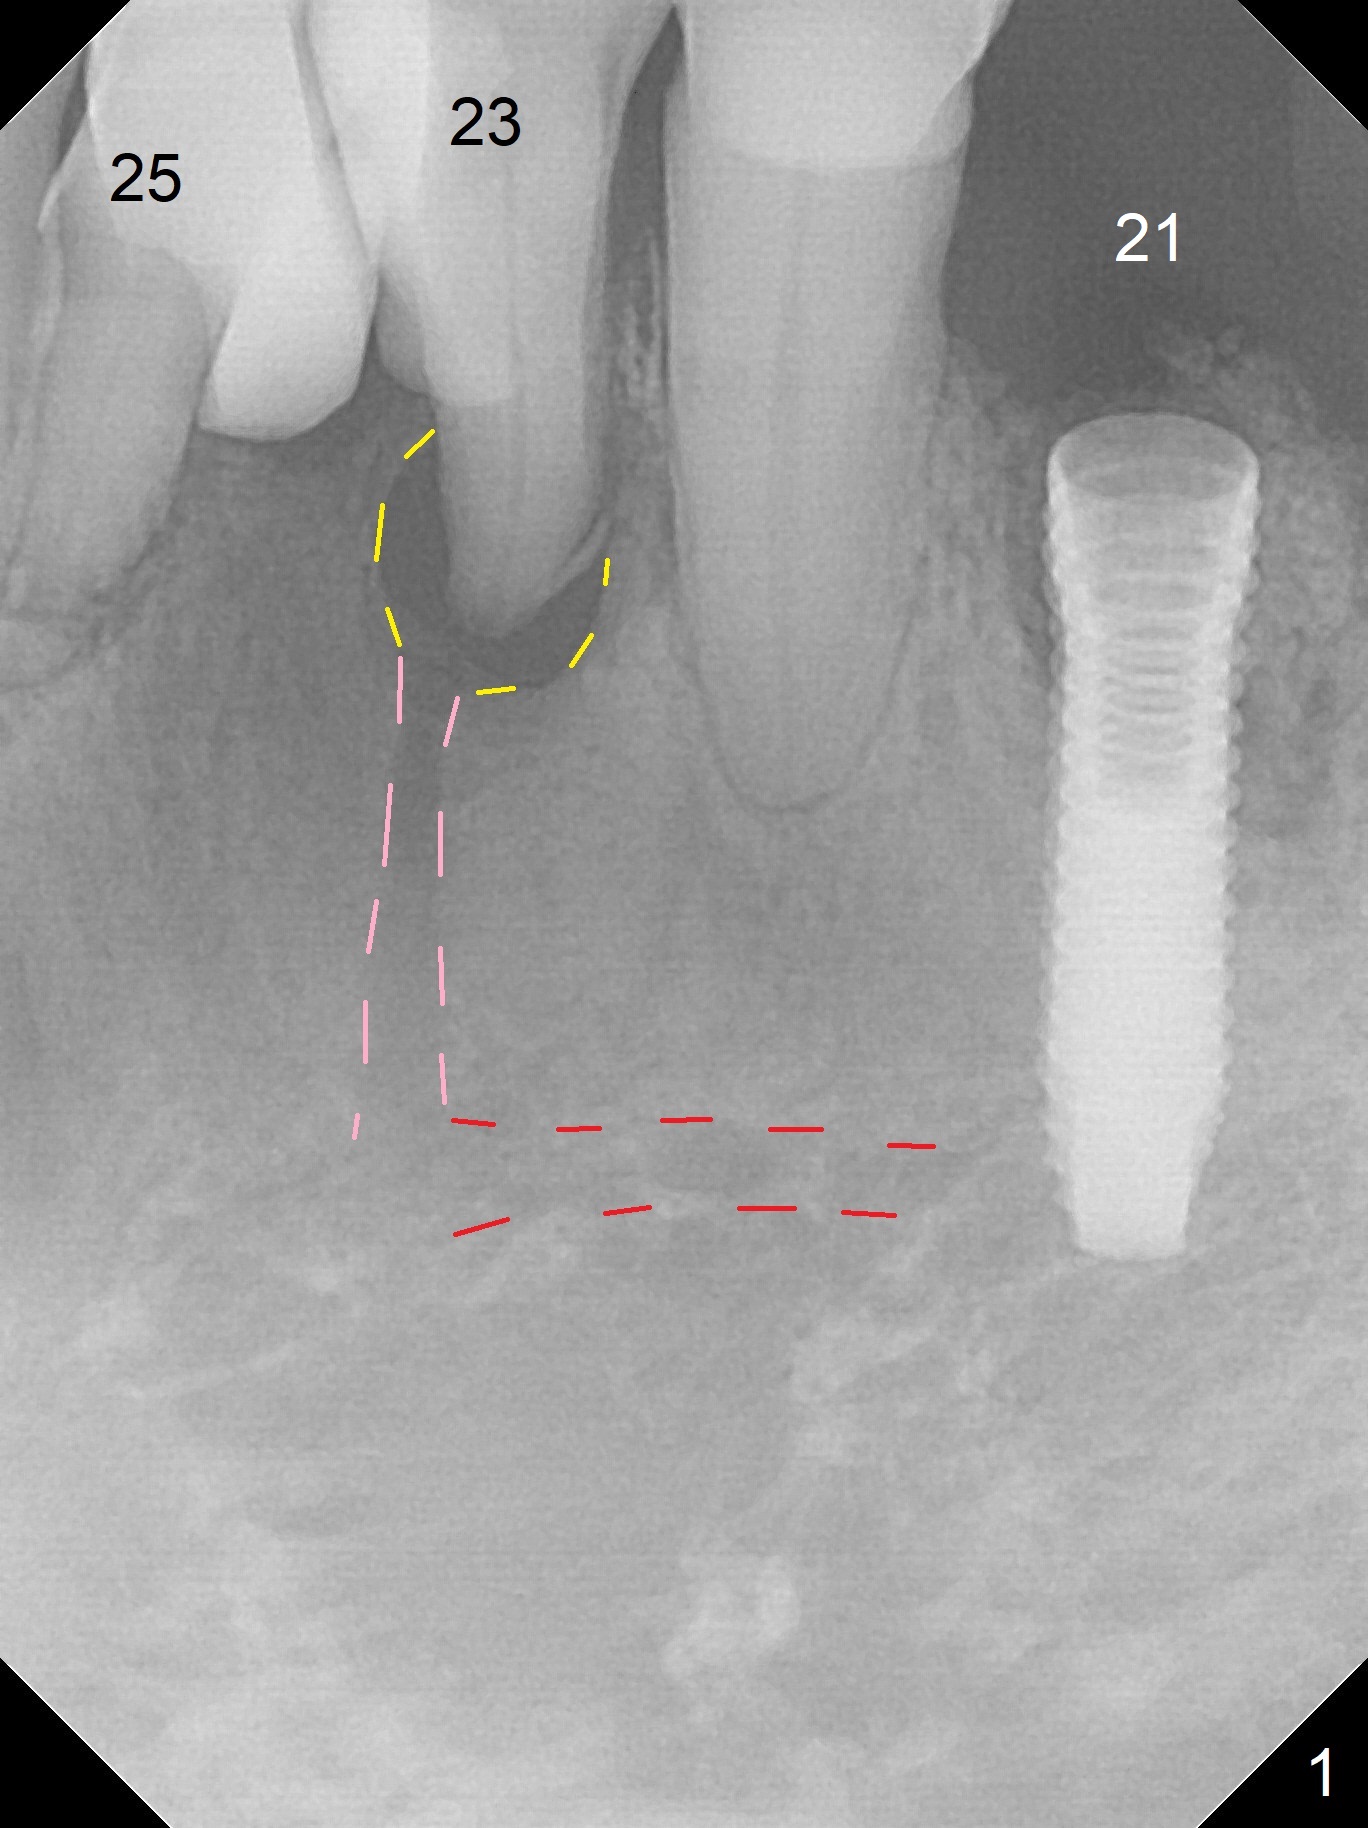

A 73-year-old man will return for #23 and 25 implants following ones at #21 and 31. Probably due to large periapical radiolucency at #23 (Fig.1 yellow dashed line), the terminal branch (pink) of the Incisive Canal (red) is distinct. Postop hemorrhage occurs associated with placement of a long implant at #. To prevent the complication at #23, a 14 mm long 1-piece implant (Fig.3) seems to be safer than 16 mm one (Fig.2). Seven mm in the native bone (Fig.3) should provide with sufficient primary stability. A temporary crown will be fabricated at #31. If the provisional at #21 is unstable, impression may be necessary for #21 and 31. Initiate osteotomy using visual and tactile acuity and double check the position and trajectory with RPD and X-ray. It might be preferable to extract the malpositioned incisor to give the remaining one the best 3-dimensional reference. Prepare 2 of 1-piece implant kits as well as angled one.